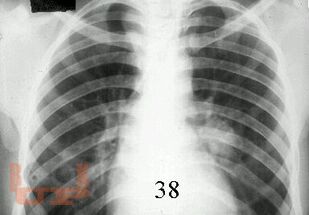

Первичный туберкулез

В предлагаемом учебно-методическом пособии рассматриваются вопросы клиники, диагностики, дифференциальной диагностики первичных форм туберкулеза.

Учебно-методическое пособие предназначено для студентов, обучающихся по специальности «Лечебное дело», «Педиатрия».